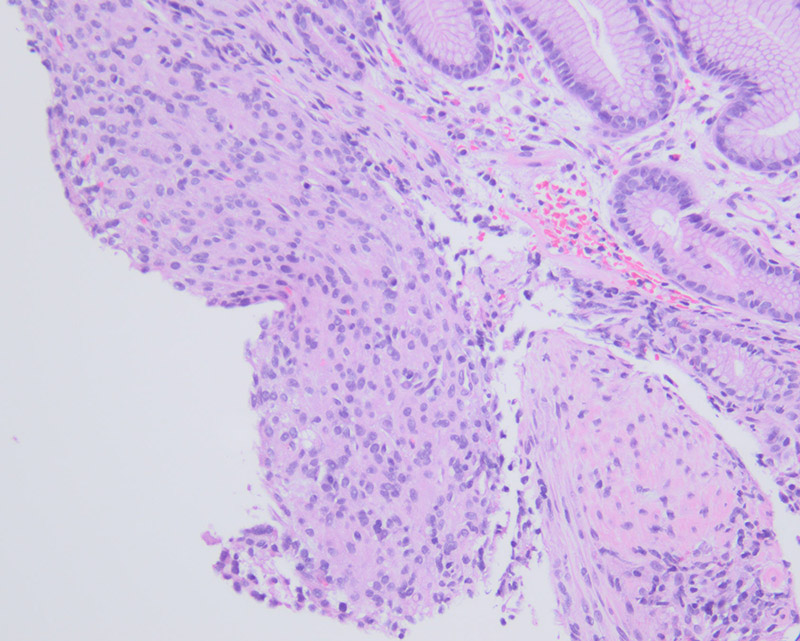

The polyp was non-obstructing and not actively bleeding; biopsies were taken of this polyp. Histologically the biopsy specimen demonstrated a proliferation of uniform mixed epithelioid and spindle-epithelioid cells amongst antral-type mucosa (Figures 2, 3). No significant pleomorphism or mitotic figures were identified. Immunohistochemical stains for DOG1 and c-Kit (CD117) were positive (Figures 4 and 5, respectively). A subsequent wedge resection of the stomach to include the lesions was performed and confirmed the original biopsy diagnosis (Figure 6). Molecular testing for c-Kit and PDGFRA were performed and were negative.